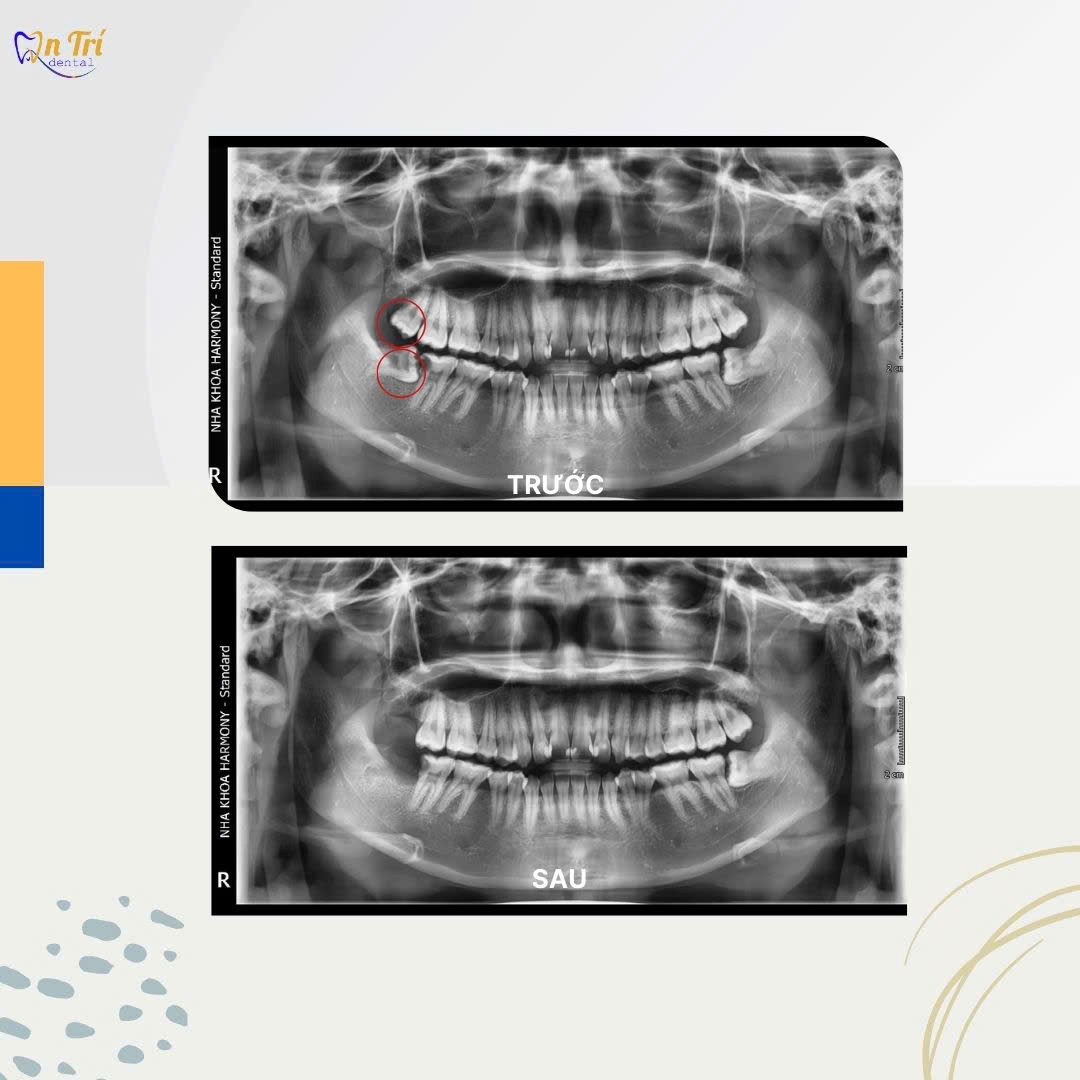

HÌNH ẢNH THỰC TẾ TRƯỚC - SAU ĐIỀU TRỊ NHỔ RĂNG KHÔN

Khách hàng Nguyễn Chí Tài